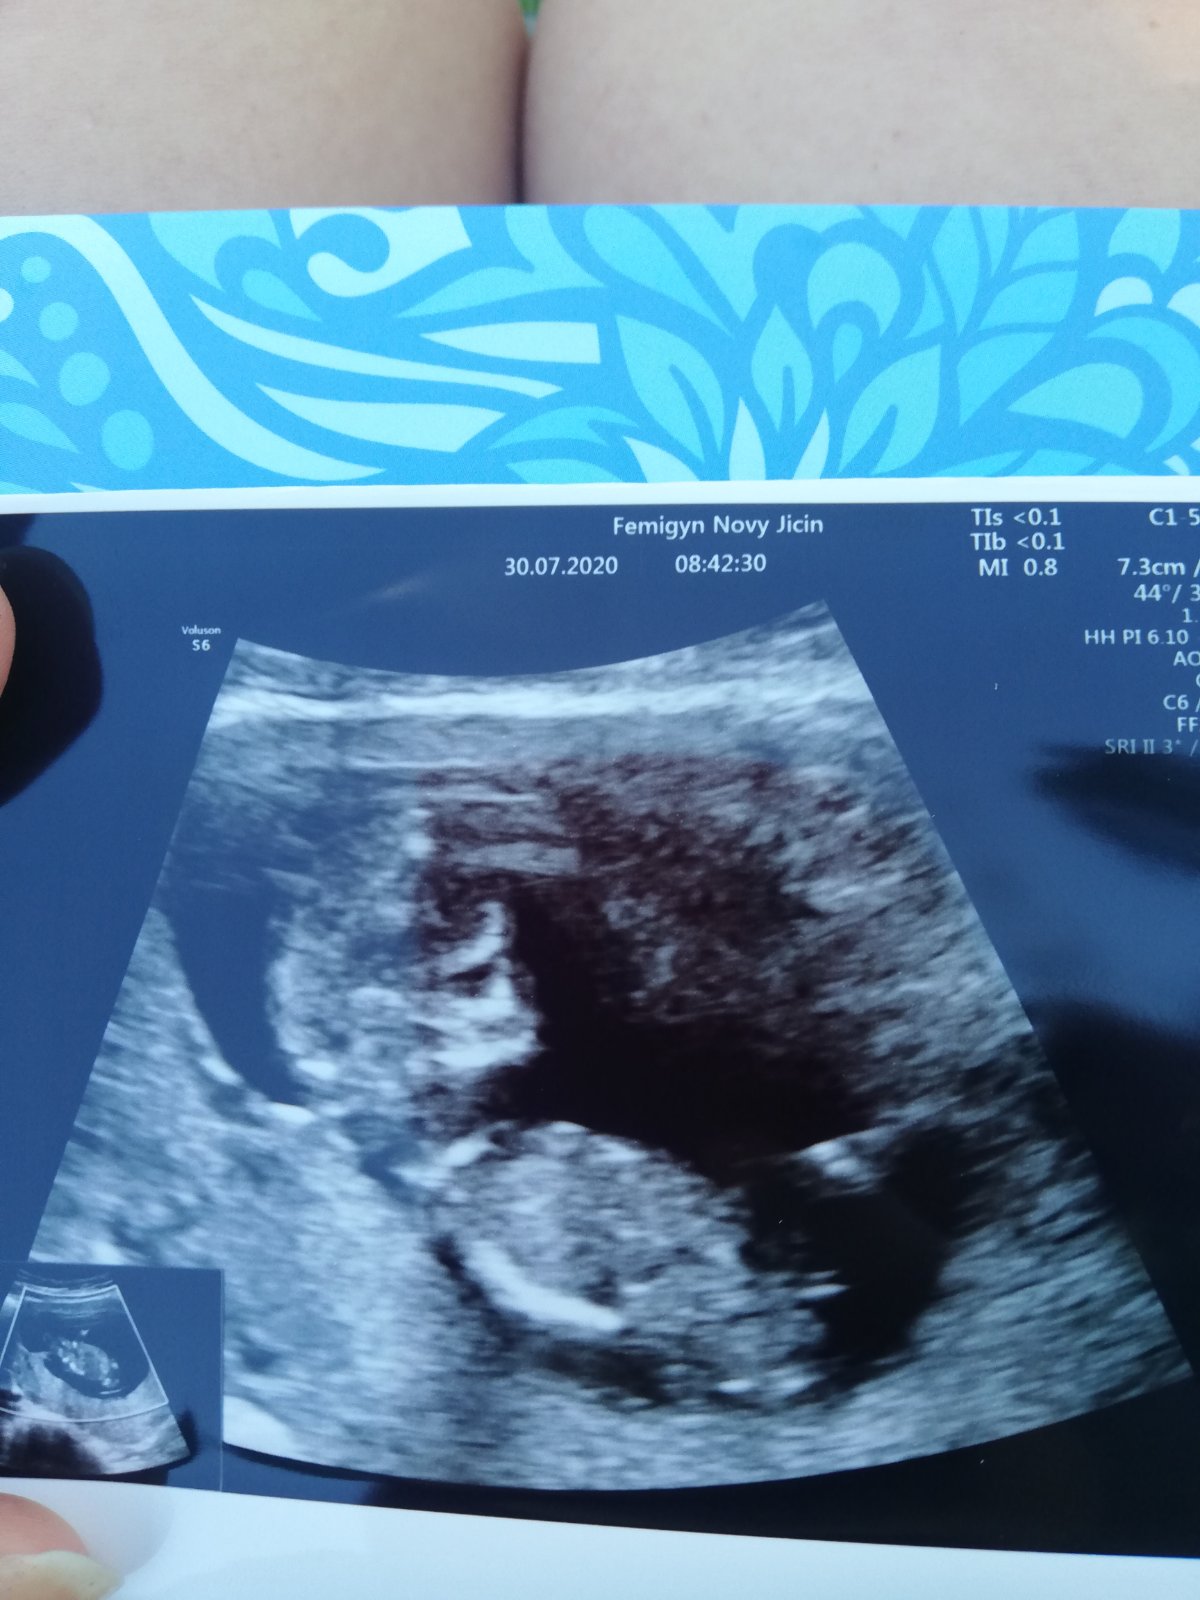

Ahoj maminky a budoucí maminky 😉 Prosím, poradila byste mi některá, co vidíte na fotce z ultrazvuku ve 20. týdnu za pohlaví? Určitě jste foteček viděly už mraky, proto vás žádám o radu...Nechci nikoho ovlivnit, proto svůj tip řeknu později 🙂 Děkuju moc!!!

@ltaborikova moc gratuluji 😍👍😍 my to porad nemame potvrzeny nebo ja nemam jasny dukaz jako jsem vzdycky mela u kluku a tak se bojim radovat a nakupovat 🎀

@verysek1 Děkuji moc, jsem šťastná 🙂 A už jste byla na tom UZ ve 20tt tam je to většinou už hezky vidět, já to teda viděla tak, že už to považuju za jistotu a 2 doktoři nezávisle na sobě už to potvrzovali tak to beru jako hotovou věc 😀 Držim pěsti!

Holka 100%